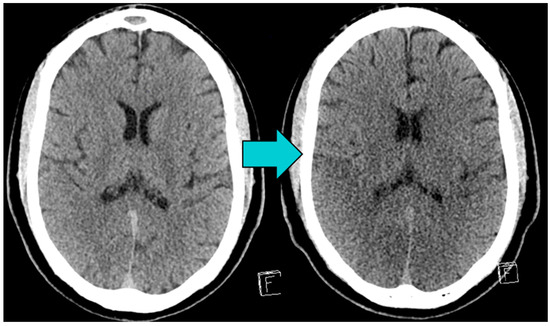

Patients were excluded if they presented with significant chronic brain defects (e.g., post-ischemic), large calcifications of the basalganglia, or if their CT scans were of poor image quality, e.g., due to artifacts. Exemplary initial and follow-up brain CTs of an included patient are shown in Figure 2.

Figure 2. Images from a patient who suffered cardiac arrest (CA) and return of spontaneous circulation (ROSC). The initial unenhanced brain CT, taken < 6 h after ROSC (left image), shows no acute pathologies and no early signs of hypoxic-ischemic brain injury (HIBI). The follow-up brain CT (right image), taken 3 days after ROSC, shows global brain edema with diminished grey-matter white-matter differentiation and narrowed liquor rooms as signs of HIBI.